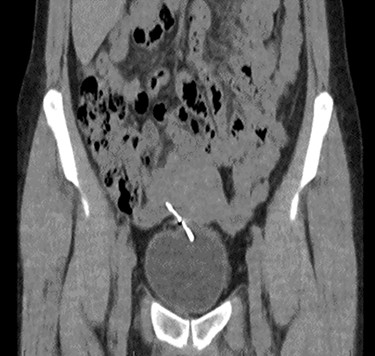

Computed tomography (CT) scan including a urographic phase revealed an IUCD in the vesico-uterine space, with one horn embedded into the bladder (Figs 2–4).

Sagittal CT urinary tract image demonstrating the device lying between uterus and bladder.